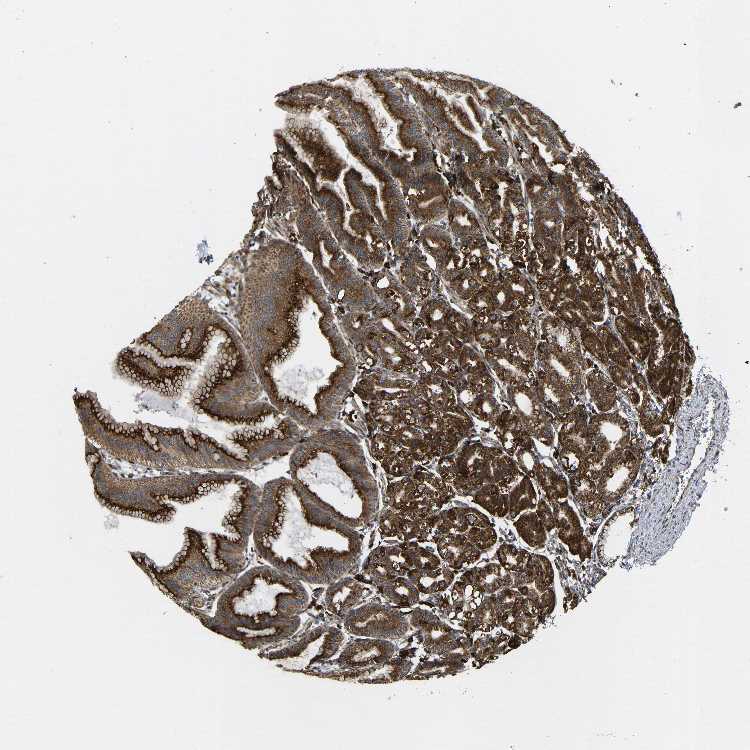

STOMACH 1 - Antibody stainingi

Antibody staining in the annotated cell types in the current human tissue is reported as not detected, low, medium, or high, based on conventional immunohistochemistry profiling in selected tissues. This score is based on the combination of the staining intensity and fraction of stained cells.

Each image is clickable and will lead to virtual microscopy that enables deeper exploration of all samples and also displays staining intensity scores, fraction scores and subcellular localization as well as patient and tissue information for each sample.

Antibody HPA014030

Glandular cells High